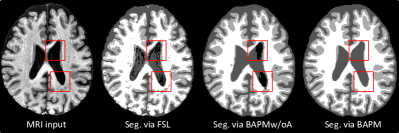

Refer to caption

Figure 2: MRI reconstructions (rec.) and tissue segmentation (seg.) maps of white matter, gray matter and cerebrospinal fluid produced our BAPM and FSL on (1) LLD study and (2) DM study.

In the proposed BAPM, the pre-trained pretext model can also be used for MRI reconstruction and brain tissue segmentation in downstream studies. So, we further qualitatively and quantitatively evaluate the performance of the pretext model via two groups of experiments. We first visualize the results of our pretext model on target MRIs from LLD and DM studies in MRI reconstruction and tissue segmentation in Fig. 2. The brain segmentation maps generated by FSL are also visualized for comparison. Note that T1-weighted MRIs in the LLD study are collected from two sites and have more inconsistent image quality when compared to those from DM.

From Fig. 2, we have several exciting observations. First, our reconstructed MRIs have more consistent image quality than the original ones. For instance, our methods help remove some noise (see ID: 1251 from LLD) and motion artifacts (see ID: 1653 from LLD) in the reconstructed images. This may imply that using MRI reconstruction as an auxiliary task can guide the encoder to extract more general features that are resistant to noise and artifacts. Second, the segmentation maps generated by our pretext model are generally better than those of FSL in most cases, especially for those cortical surface areas in the two studies. For instance, the WM region in segmentation maps generated by BAPM is much cleaner than that of FSL, indicating that our model is not sensitive to noise in MRI. Even for the LLD study with significant inter-site data heterogeneity, the boundary of WM and GM produced by BAPM is more continuous and smoother, which is in line with brain anatomical structures. Besides, for MRIs (IDs: 1240, 1334, and 1653 from LLD) with severe motion artifacts, our model can produce high-quality segmentation maps that are even comparable to those of MRIs without motion artifacts. This demonstrates that our model is robust to noise and motion artifacts in both reconstruction and segmentation tasks. The underlying reason could be that the pretext model is trained on large-scale MRIs and thus has good generalization ability when applied to MRIs with different image quality. Additionally, our BAPM can achieve better segmentation results in many fine-grained brain regions than FSL, such as the putamen region (see CN001 and MCI003 from DM) and the vermis region (see CN004 from DM). These results demonstrate the excellent adaptability of the pretext model when applied to downstream tasks for image reconstruction and tissue segmentation.

Inspired by previous studies [54, 22], we augment the source MRIs using random affine transformation, random blur, random noise, random bias field, and random motion artifact. We now study the effect of such data augmentation strategy by comparing our BAPM with its variant (called BAPMw/oA) without using augmented data. In Fig 6, we visualize a typical MRI with motion artifacts and its segmentation maps generated by FSL, BAPMw/oA, and BAPM. It can be observed from Fig. 6 that the segmentation maps of three tissues produced by BAPM and BAPMw/oA are generally better than those of FSL, suggesting the effectiveness of our methods in suppressing noisy information in original MRIs to some extent. Besides, as illustrated in red boxes in Fig. 6, BAPMw/oA and FSL misidentify some CSF sub-regions as background, while BAPM can generate very good segmentation results in these regions. It implies that the proposed data augmentation strategy used in BAPM helps increase the diversity of input MR images, thus facilitating high-quality tissue segmentation.

Figure 6: Segmentation (Seg.) results of three methods.